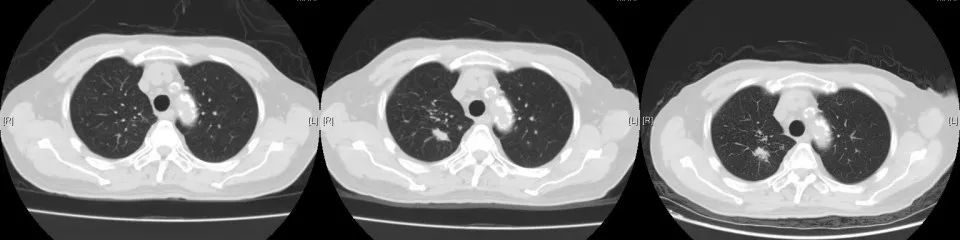

2018年1月复查胸部CT:右肺占位较前增大,余无明显特殊不适。外院再次行肺穿刺活检,病理:右肺组织见癌转移(符合膀胱癌肺转移)。2018年3月14-29日于我院行肺转移灶局部放疗。2018年5月15日-7月11日予标准方案化疗2周期。期间病情稳定。2018年10月复查,局部肺转移灶增大进展、且出现肺新转移灶,评估疗效PD,行NGS全基因检测,根据检测结果,即选用阿法替尼口服行靶向治疗。

2020年3月复查,病灶再次进展,参考前次基因检测结果,结合临床情况,即开始给予口服吡咯替尼80mg每日一次,2020年4月25因心梗住院治疗。停药约2周。复查示原转移灶稍增大,考虑是否与停药有关,故继续维持吡咯替尼治疗。期间多次复查,病情稳定。局部考虑缓慢进展可能。但综合考虑临床情况,仍继续维持原方案治疗。

CT变化: